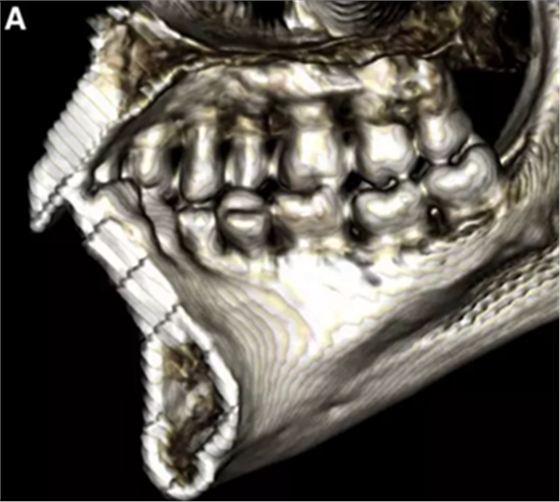

然而,CBCT成像也具有較大的限制:有限的分辨率,牙體組織的不準(zhǔn)確表現(xiàn),以及當(dāng)患者在咬合位或者完全牙尖交錯(cuò)位CBCT掃描時(shí),上頜骨和下頜骨牙齒之間發(fā)生的混合(圖1)。 這種混合使上頜骨與下頜骨牙齒的自動(dòng)分離復(fù)雜化,并且由于咬合解剖結(jié)構(gòu)和細(xì)節(jié)的不準(zhǔn)確而使人工分離變得困難。

圖1. 在CBCT中咬合時(shí)上頜牙齒和下頜牙齒咬合面的混合和咬合細(xì)節(jié)的喪失。